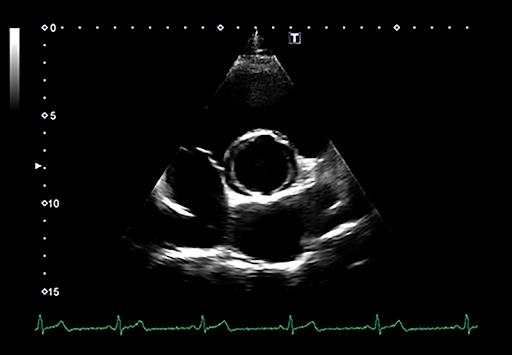

Надежная диагностика с выдающимся качеством изображения

Только самое лучшее качество изображения позволяет быстро и с уверенностью поставить диагноз. Каждая из уникальных технологий визуализации Xario обеспечивает лучшую четкость и разрешение за счет снижения шума, усиления сигнала и улучшения визуализации.

Canon Medical Systems' High Density Architecture формирует основу для превосходного качества изображения и позволяет вам видеть больше деталей и делать больше исследований. Благодаря всесторонним возможностям улучшения изображения и настройке глубины до 40 см, Canon Medical Systems, несомненно, является лидером в предоставлении лучших в своем классе изображений для диагностики различных заболеваний.

Аппараты Xario 100 оснащены передовыми технологиями визуализации и инструментами для проведения количественного анализа, которые расширяют возможности диагностики, повышая уверенность в написании заключений и постановке диагноза.

Технология Precision Imaging улучшает определение границ и делает края структур более четкими.

Технологии для кардиоваскулярной визуализации

Tissue Enhancement

Эксклюзивная технология Tissue Enhancement позволяет проводить исследование у пациентов с затрудненной визуализацией за счет повышения однородности изображения и четкости очертания границ эндокарда.